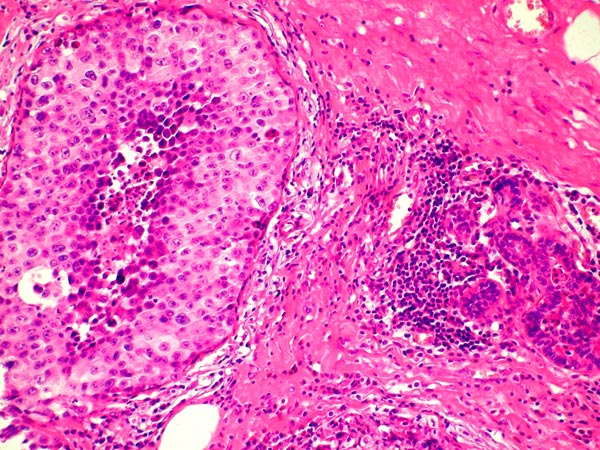

Metastáza maligního melanomu do prsu napodobující komedonový DCIS